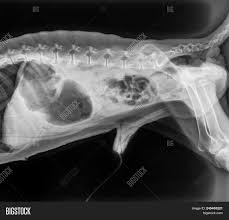

1 Abdominal Positioning Small Animal Special Procedures Chapters from slidetodoc.com The corpus spongiosum is a vascular tissue sleeve surrounding the urethra. 2021 ultimate guide to dog anatomy. This veterinary anatomical atlas includes selected labeling structures to help student to understand and discover animal anatomy (skeleton, bones, muscles, joints, viscera, respiratory system. Anatomy synonyms, anatomy pronunciation, anatomy translation, english dictionary definition of anatomy. As the pace of veterinary advancement accelerates, even the most experienced veterinary teams are challenged to keep up with all the changes that impact their practice. Browse our extensive yoga pose library, with a vast collection of basic poses, advanced poses, seated and standing poses, twists, and bandha techniques. A muscular partition separating the. Browse among thousands of answers from verified vets and pet experts to common health, behavior, nutrition and care questions about dogs and cats.